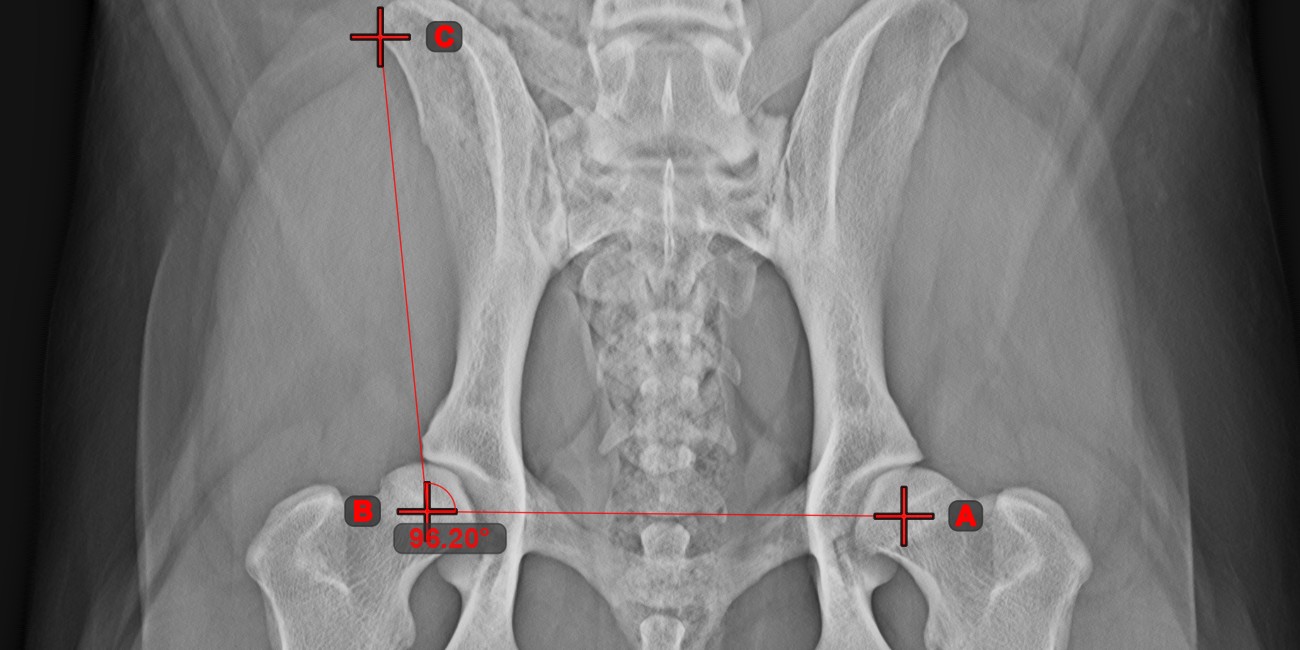

Angle of Lines¶

Select the tool from the left toolbar and assign it to one of the available mouse buttons. Start by selecting the first line from the ones already drawn on the scene, or place the start and end points to create the line. Follow the same steps for the second line of the measurement. The angle between the two lines will be automatically calculated.

Modify the start and end points of both lines by using the Select/Move Item tool. The angle between the two lines will be automatically recalculated.

Information

If two lines do not intersect directly, the angle of their extended projections on the scene will be calculated.